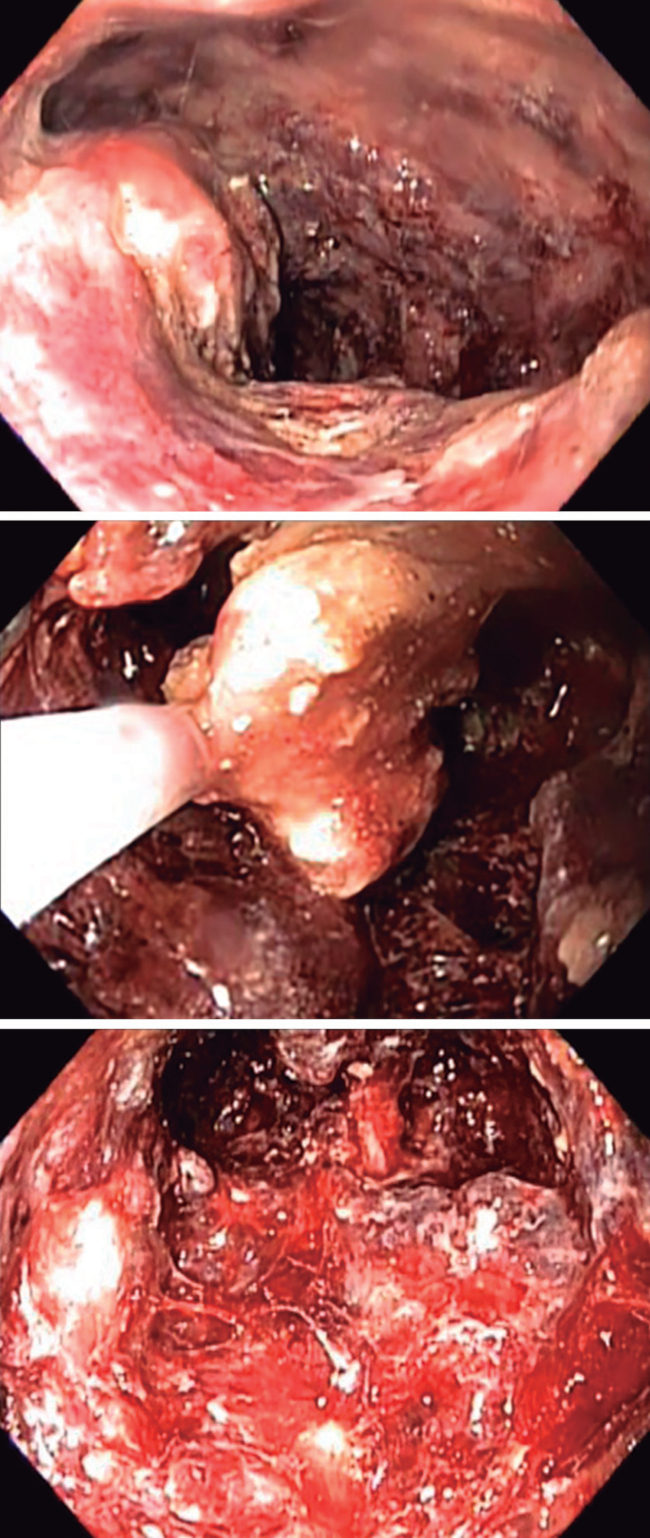

Se realiza procedimiento en quirófano, bajo anestesia, en posición supina. Se avanza alambre guía a través del drenaje percutáneo hacia la cavidad bajo guía fluoroscópica. Posteriormente, se retira el drenaje y se procede a dilatar el tracto con pinza Kocher. Se introduce stent metálico esofágico autoexpandible (120 x 26 x 20 mm). La luz del stent se dilata con balón de 12 mm en región que corresponde a aponeurosis. Se realiza sutura de la prótesis a la piel y se evidencia salida de material purulento hacia el exterior. Se aborda con un endoscopio a través del stent esofágico hacia la cavidad (Figura 3), observando cavidad con tejido necrótico multicompartimental (Figura 4A). Se realiza necrosectomía por desbridamiento mecánico de residuos necróticos con asa y lavado con solución salina de todos los compartimientos (Figura 4B). En sesión subsiguiente, por evidenciarse presencia de material necrótico subyacente al stent, se retira hacia el exterior 3 cm, continuando con necrosectomía. Se realizan sesiones cada 48 horas con un total de cinco, hasta lograr visualizar ausencia de material necrótico, con paredes constituidas por tejido de granulación, indicando vitalidad del mismo (Video) (Figura 4C). Todos los procedimientos fueron realizados por un solo operador.